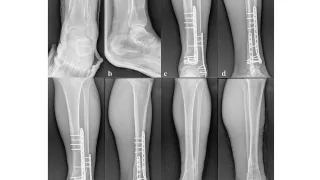

大腿骨頚部骨折の闘病日記

手術日+727日目 2026/2/24(火)(骨折から2年)